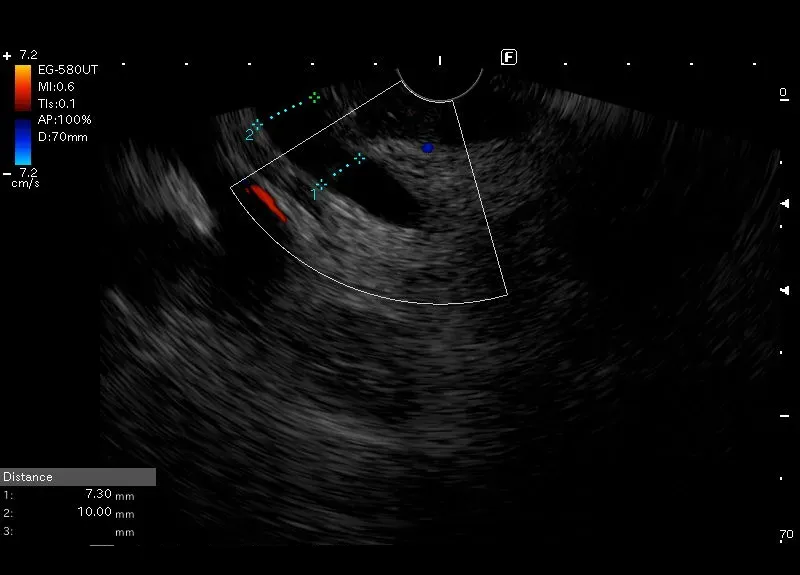

Odcinkowe poszerzenie

przewodu żółciowego wspólnego do 10 mm w stosunku do pozostałego

odcina o szerokości 7mm , prawdopodobnie o podłożu pozapalnym.